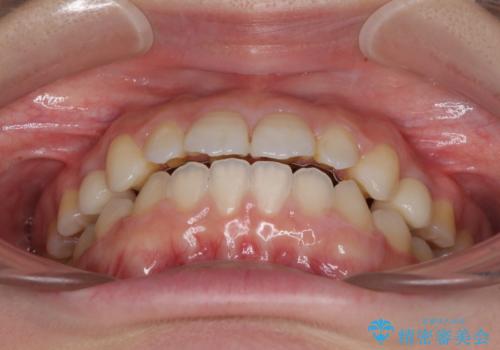

- 歯の欠損による隙間だらけの歯並びを気にして来院された患者様です。

上顎左右1本ずつ欠損していたため、歯列矯正により欠損部位にスペースを集め、その後欠損部位をインプラントにて補綴することとしました。

インビザラインによる矯正治療も提案しましたが、長時間の装着や自己管理が難しいとお考えで、ワイヤーによる矯正治療を行いました。

歯並びは比較的早めに整いましたが、インプラントを埋入するにあたって前後の歯根位置を改善する必要があり、矯正治療に期間を要することとなりました。